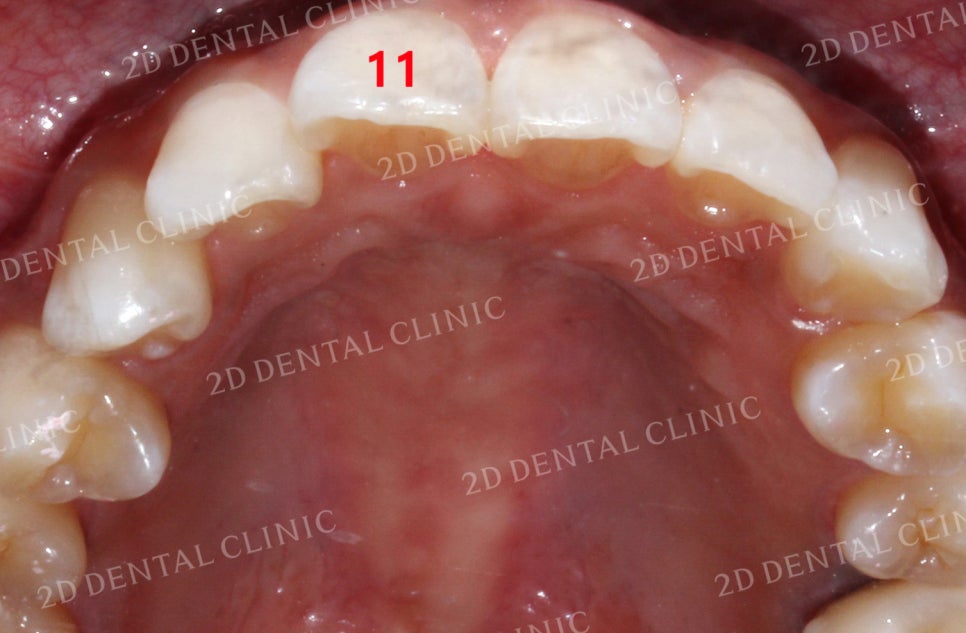

상악의 설측면 사진입니다.

교정 전 총생으로 인해

순측으로 틀어졌던 11번 치아가

교정 후 올바른 위치로

돌아오게 되었습니다.

특히 11번과 12번 치아의

총생이 잘 보였는데 교정 후

고르게 바뀌었습니다.